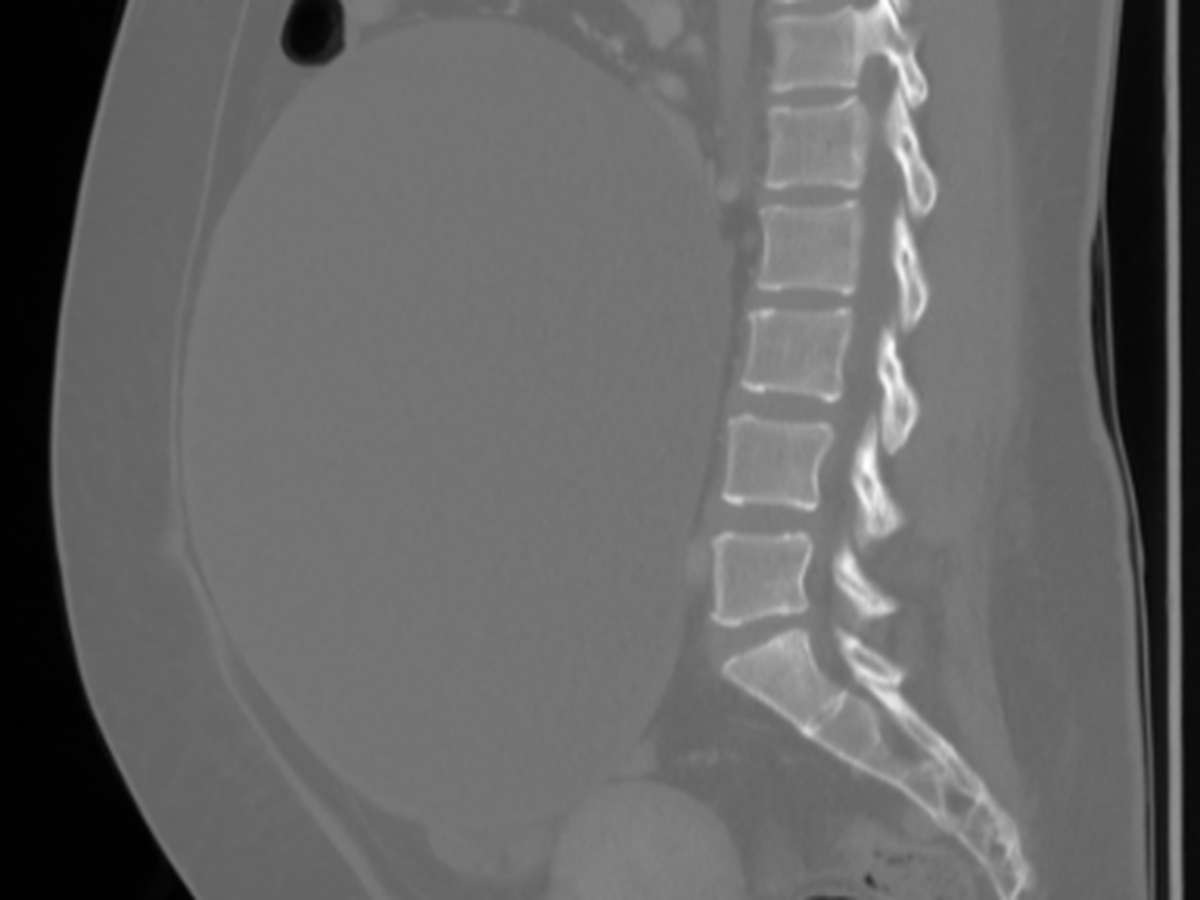

My name is Julieta. I’m currently in Canada and recently received heartbreaking medical news — I have a 25 cm cyst on my right ovary that could rupture at any moment. I also have another smaller cyst, about 3.8 cm on my left ovary.

A few days ago, I had to be admitted to the emergency room because of severe abdominal pain. I initially thought it was related to IBS (Irritable Bowel Syndrome), but after several tests and scans, the doctors discovered the true cause, the large ovarian cyst that’s now putting my health at serious risk.